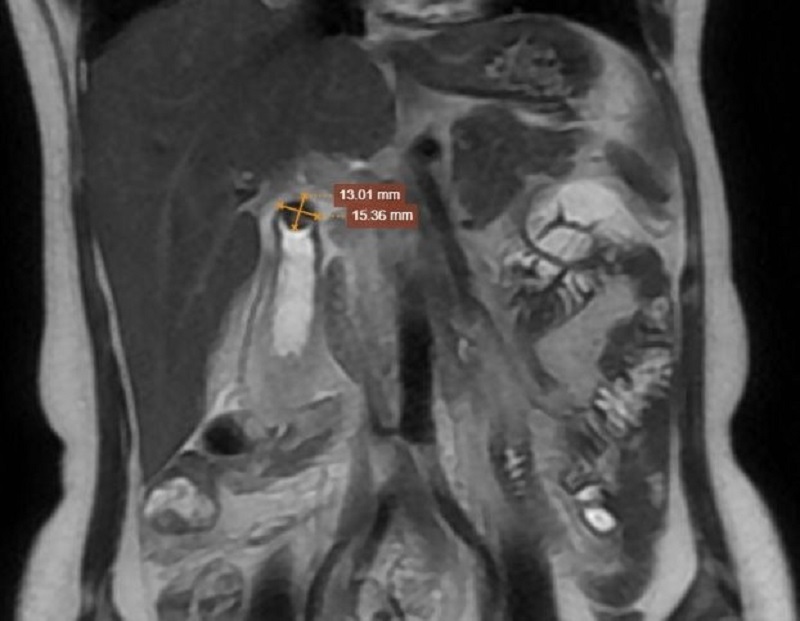

Chụp MRI cho hình ảnh cổ túi mật có sỏi kẹt kích thước xấp xỉ 13x15mm

- Chụp cộng hưởng từ: Túi mật có kích thước xấp xỉ 120x30mm. Thành túi mật dày 9mm, giường túi mật có lớp dịch dày xấp xỉ 9mm, theo dõi có vị trí mất liên tục thành trước vùng đáy túi mật, có thâm nhiễm mỡ xung quanh. Dịch mật: vùng đáy có nhiều sỏi tập trung thành đám kích thước xấp xỉ 41x22mm, vị trí cổ túi mật có sỏi kẹt kích thước xấp xỉ 13x15mm. Kết luận: hình ảnh viêm túi mật cấp do sỏi kẹt cổ túi mật, nghi có hoại tử thành trước vùng đáy túi mật. Gan to. Dịch khoang gan thận bên phải.